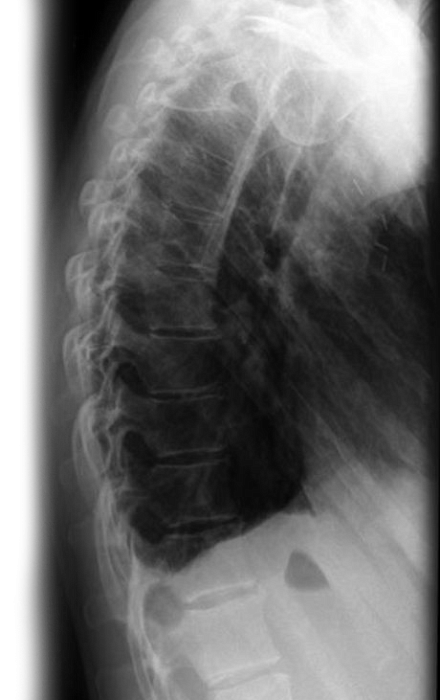

Рентгенография грудного отдела позвоночника – важный метод скринингового исследования, который позволяет оценить состояние грудного отдела позвоночника. Диагностическая услуга выполняется в двух проекциях.

18.3 Рентгенография (цифровая) грудного отдела позвоночника ( 2 проекции, запись на диск) 3 100 ₽